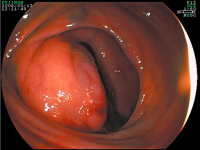

Tumor - Ösophagus

Abbildung 2: Granularzelltumor im Ösophagus

Keywords:

Endoskopie

,

Gastroenterologie

Tumor

Ösophagus